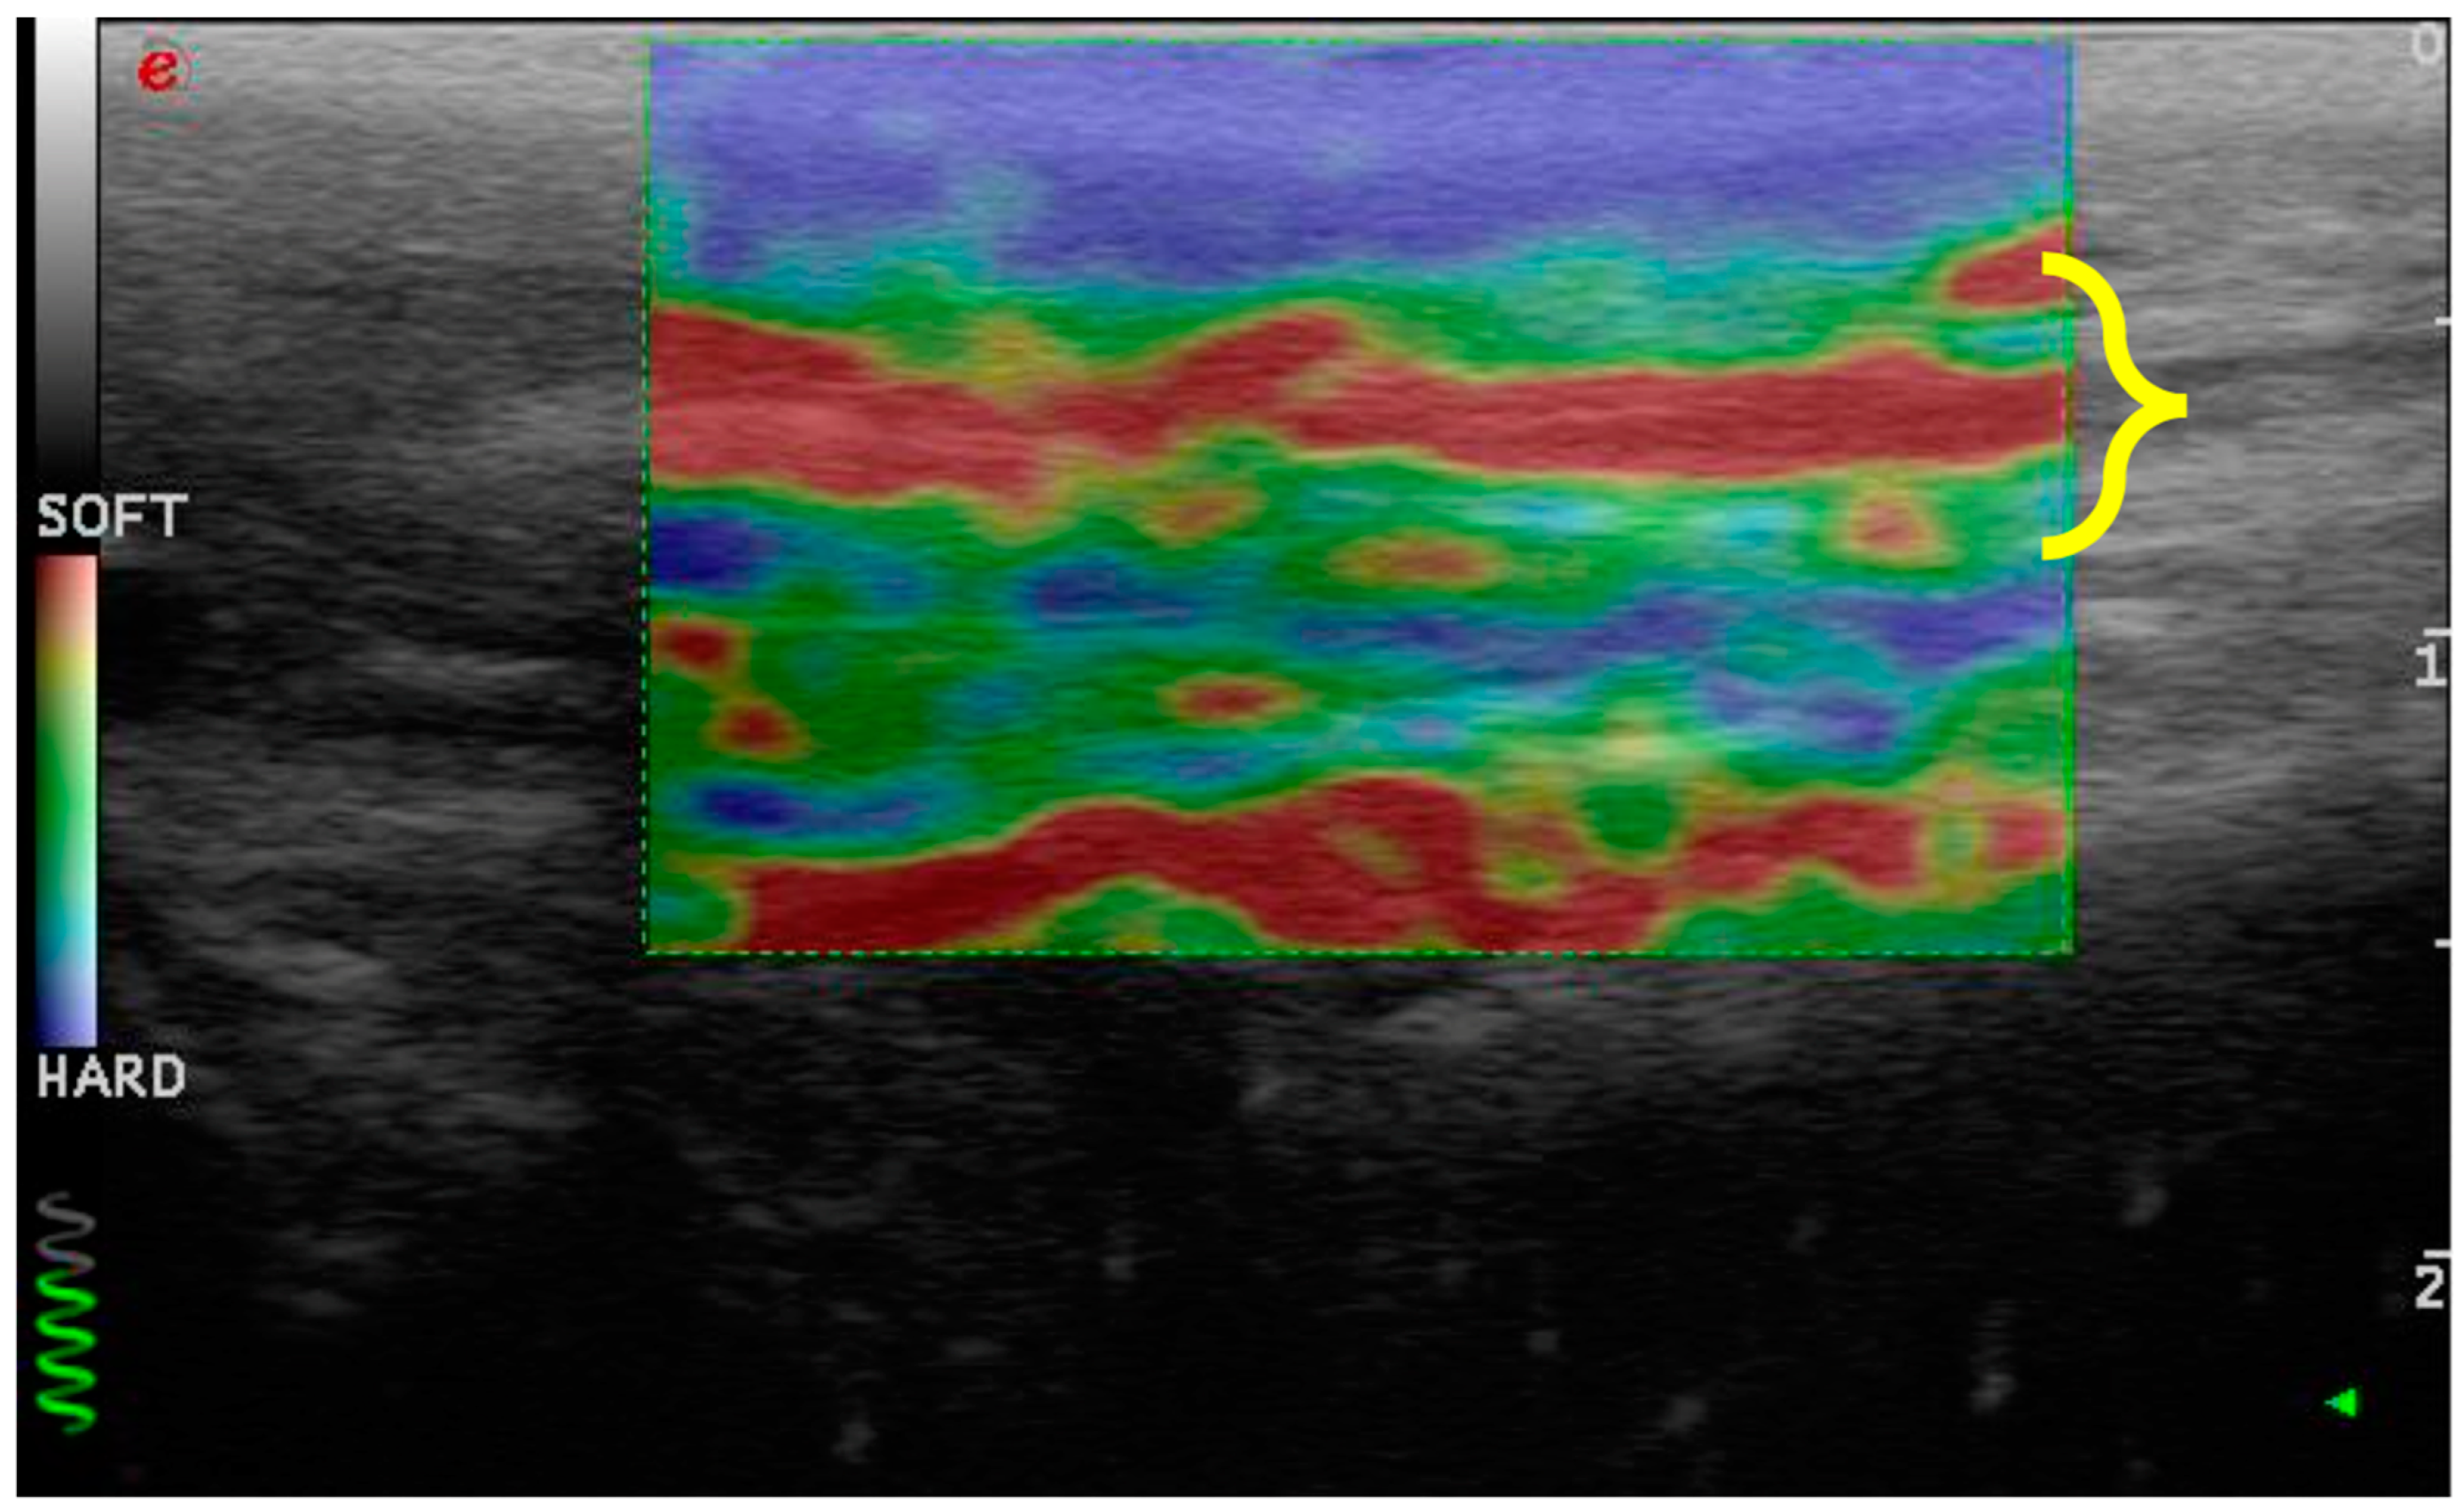

- Distinguishes between different tissues based on their rigidity. This characteristic permits an immediate visual distinction using a graphical representation. Moreover, the contrast between the different tissues is generally high.

- Allows the detection of pathologies or disorders within the same tissue, especially in tissues whose function is closely related to their structure.

- Avoids the artifacts caused by the presence of ossification or mineralization (acoustic shadowing) [29].

- Consistency between the elastogram and the underlying B-mode ultrasound image;

- Blue coloration of the skin and dermal tissue because they are harder than the patellar ligament;

- Green coloration of the marker (green coil). Thus represents real-time feedback on the quality of the strain image acquisition.